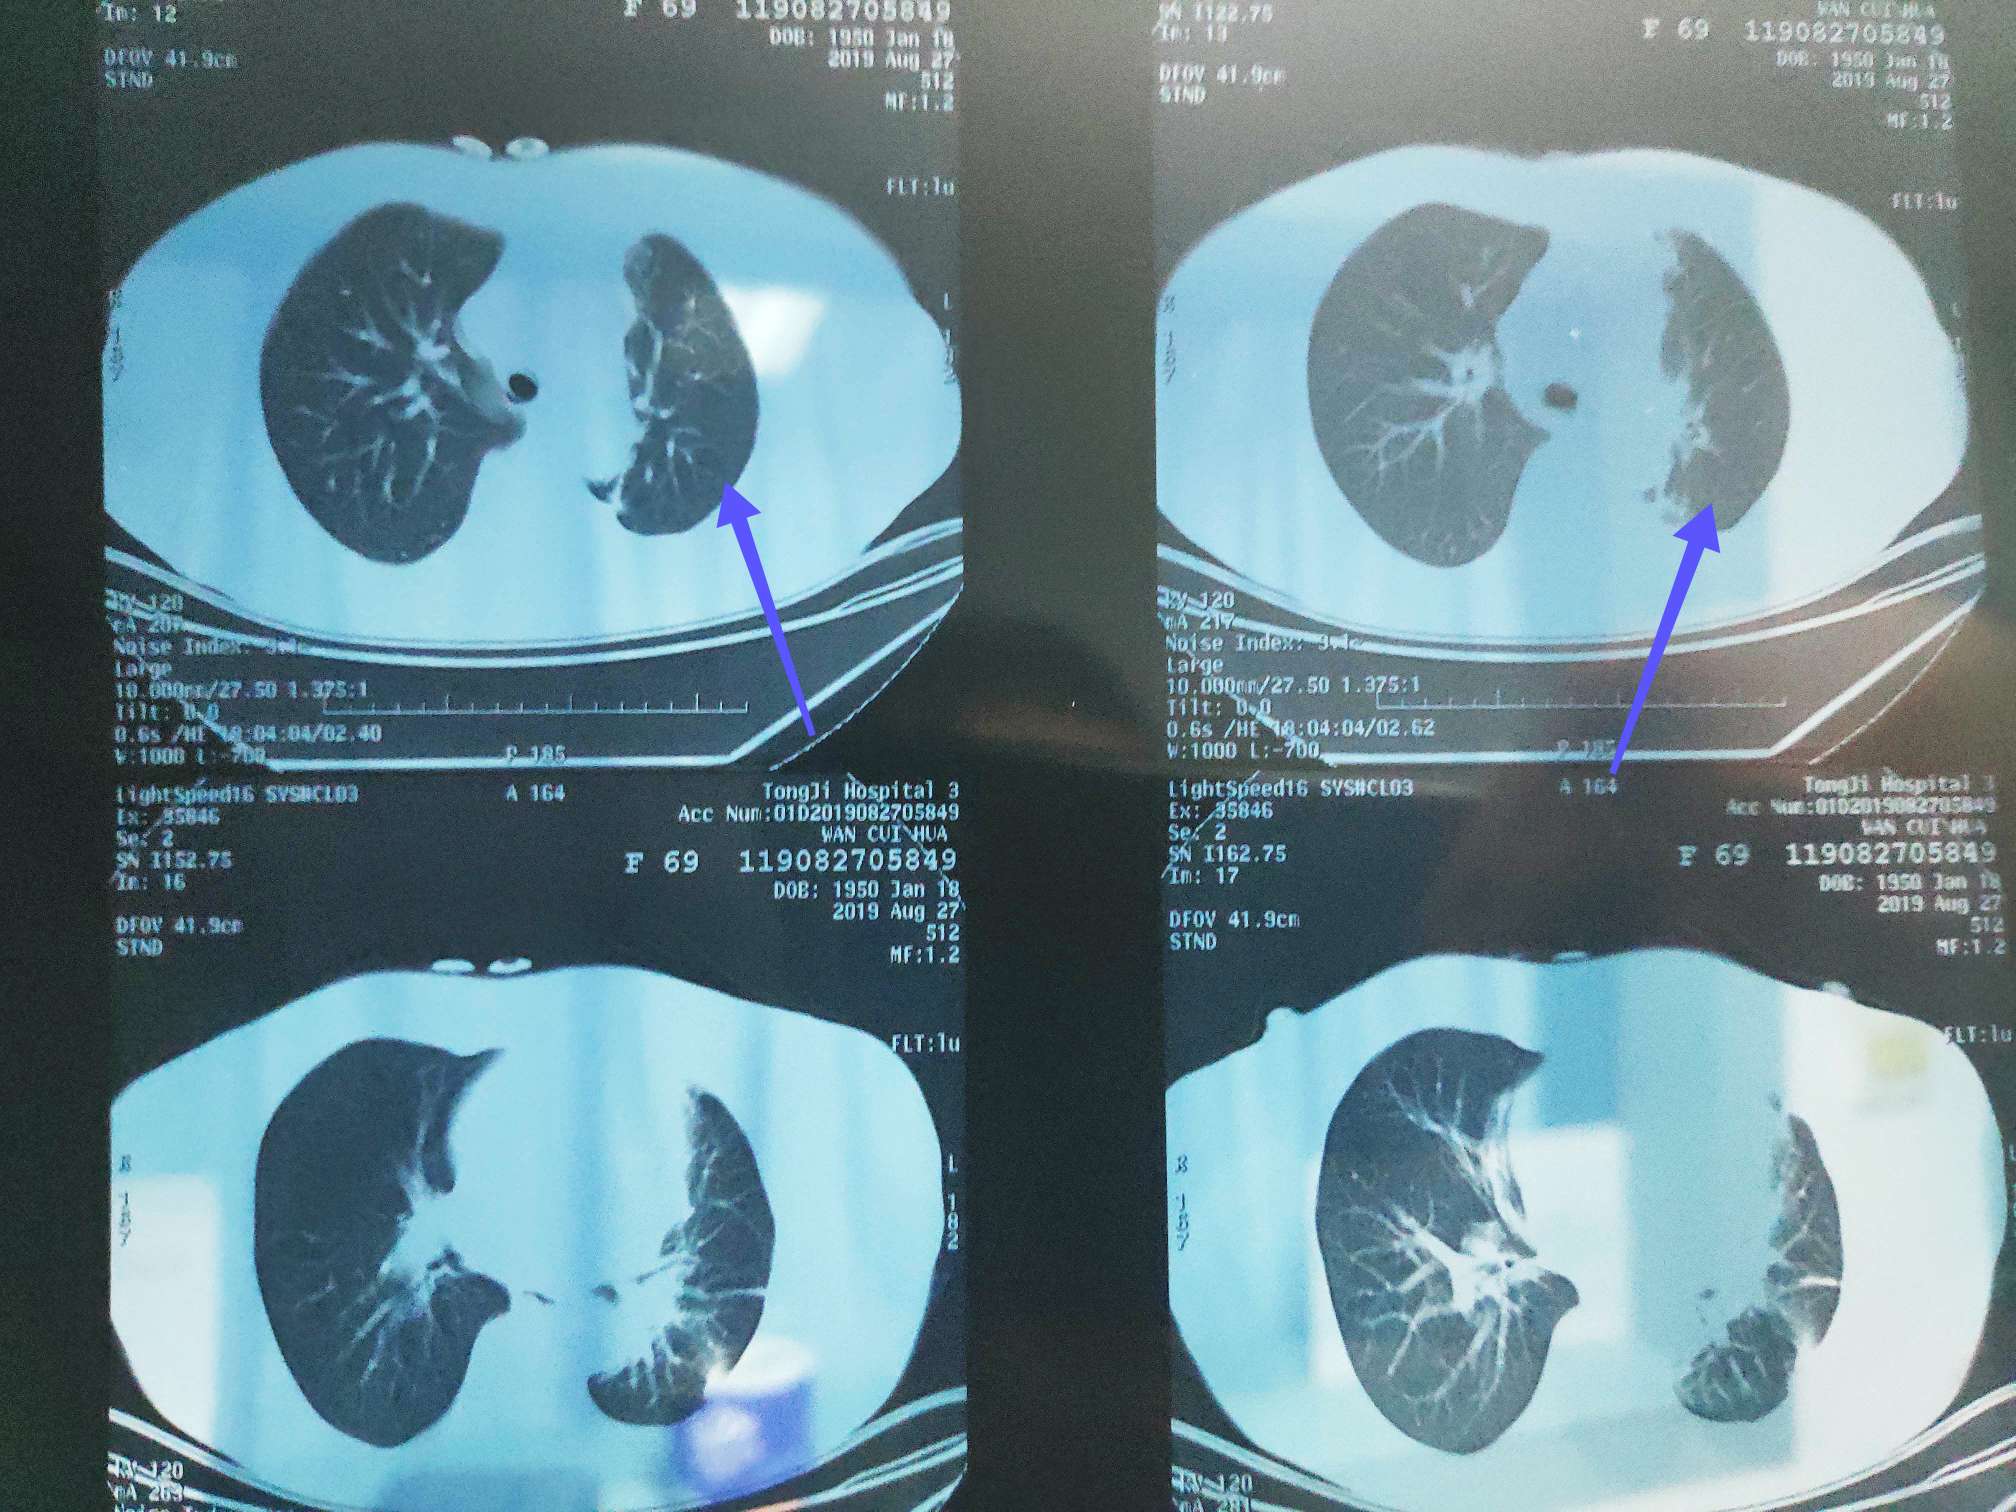

8.29二化评估全面缩小

肺部膨胀不全开始明显缓解(蓝色箭头),肺部炎症好转,医生说因为化疗使用的是多西他赛单药,二化出现这么明显好转,应该是pd1联合的效果,单药多西他赛应该不会这么明显,建议继续治疗,我提出能否下次开始单药pd1治疗,医生不赞同,说等化疗不耐受再尝试pd1单药。

三化前CT